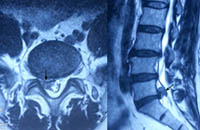

术前可见椎管内脱出的巨大髓核组织压迫神经(箭头所示) 术后3月复查MRI显示脱出的髓核组织消失,神经无明显受压